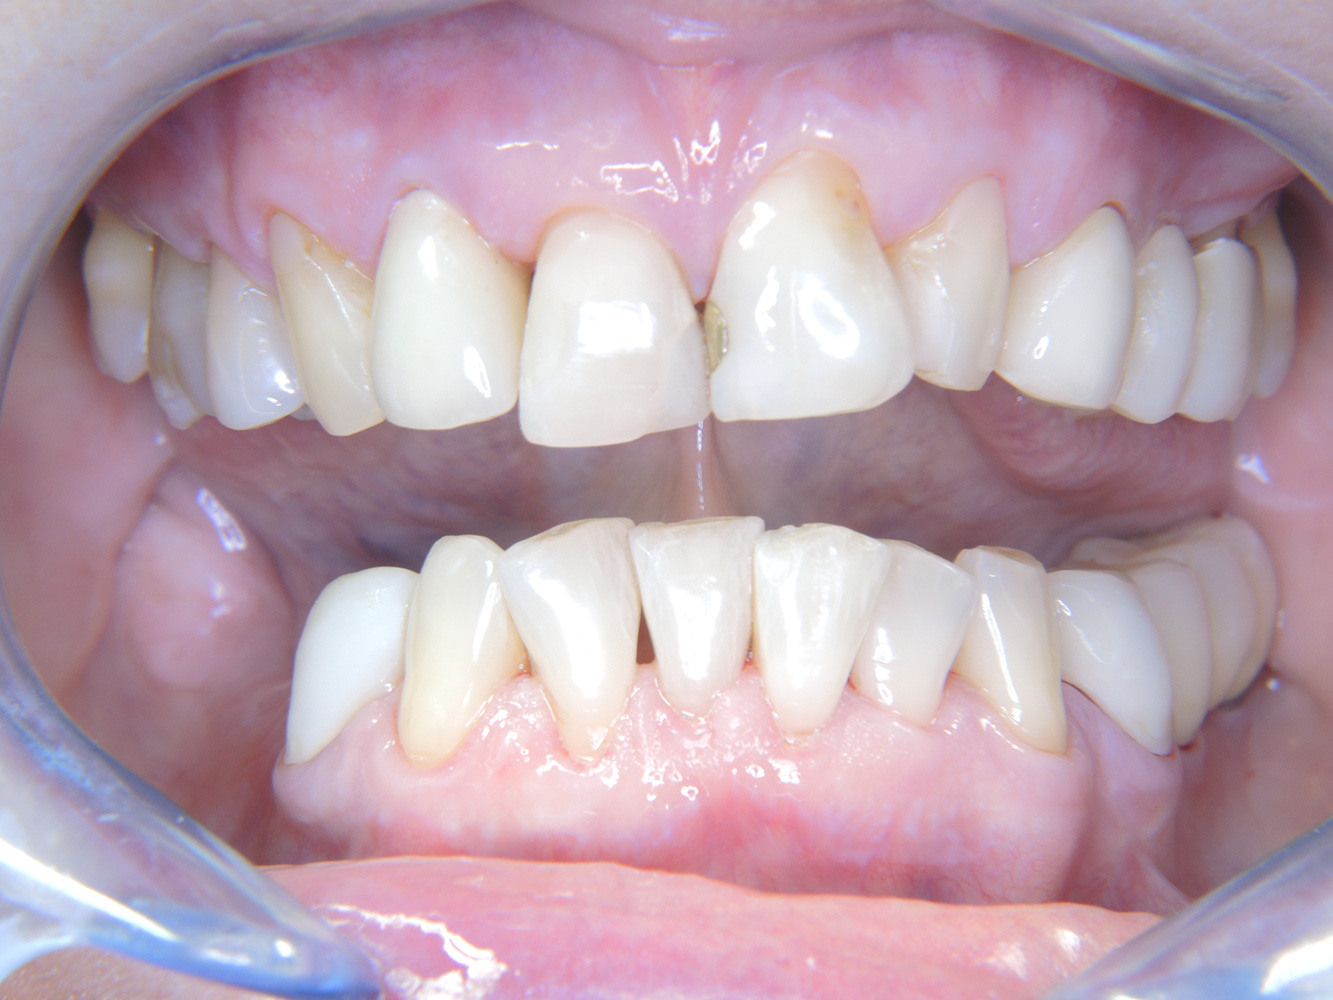

La paciente de 68 años no tiene enfermedades previas relevantes de la salud general ni toma medicación; sus hábitos alimentarios tampoco suponen un riesgo especial. La paciente tiene dos implantes (tercer cuadrante, desde hace cinco años) y una enfermedad previa periodontal (periodontitis en etapa IV, grado B) con pérdida dental. Actualmente las condiciones periodontales son estables, pero la periodontitis aumenta de manera determinante las complicaciones biológicas cuando se realizan implantes y puede ocasionar la pérdida de un implante (21). Para la sesión de profilaxis se hacen cuatro recomendaciones.